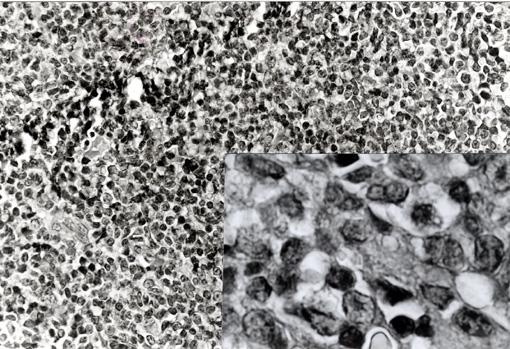

疾患(病理主体)の分類悪性リンパ系腫瘍/悪性リンパ腫

部位(臓器別)大腸/S状

検査方法ミクロ

病変の最大径(ミリ)15〜19